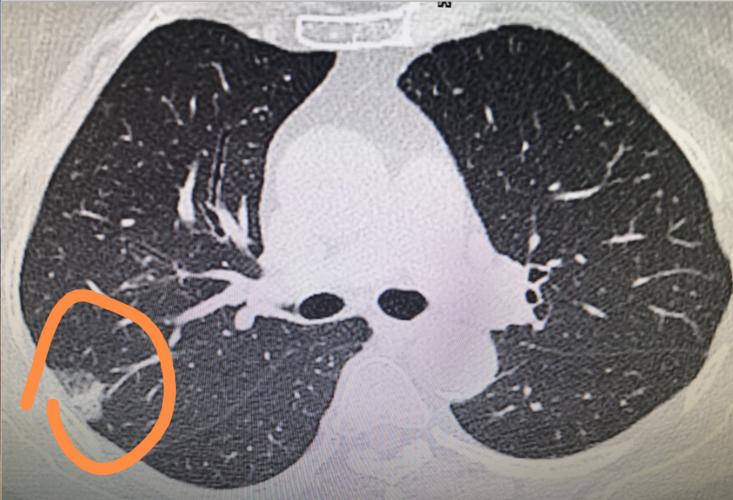

肺结节是指从肺部某个位置突然突起的小的圆形或椭圆形病变,通常直径小于3厘米,用肉眼观察一般看不到。肺结节是一种非常常见的病变,有时可以通过 chest CT 或 X光检测发现。

肺结节可以分为良性结节和恶性结节两种。良性结节通常是由于感染、肺部炎症、肿块、血管病变等引起,不会对健康造成威胁。而恶性结节则有可能是肺癌、淋巴瘤等恶性疾病的症状之一,如果不及时发现和治疗可能会对健康造成严重影响。

需要注意的是,发现肺结节并不一定表示患有肺癌或其他疾病,可能是生活中的某些因素引起的良性肿瘤或炎症。但肺结节也可能是肺癌或其他疾病的先兆,如果不及时发现和治疗,可能会带来不良后果。因此,对于发现肺部结节的患者应尽早就医,根据医生的建议进行进一步检查和治疗。